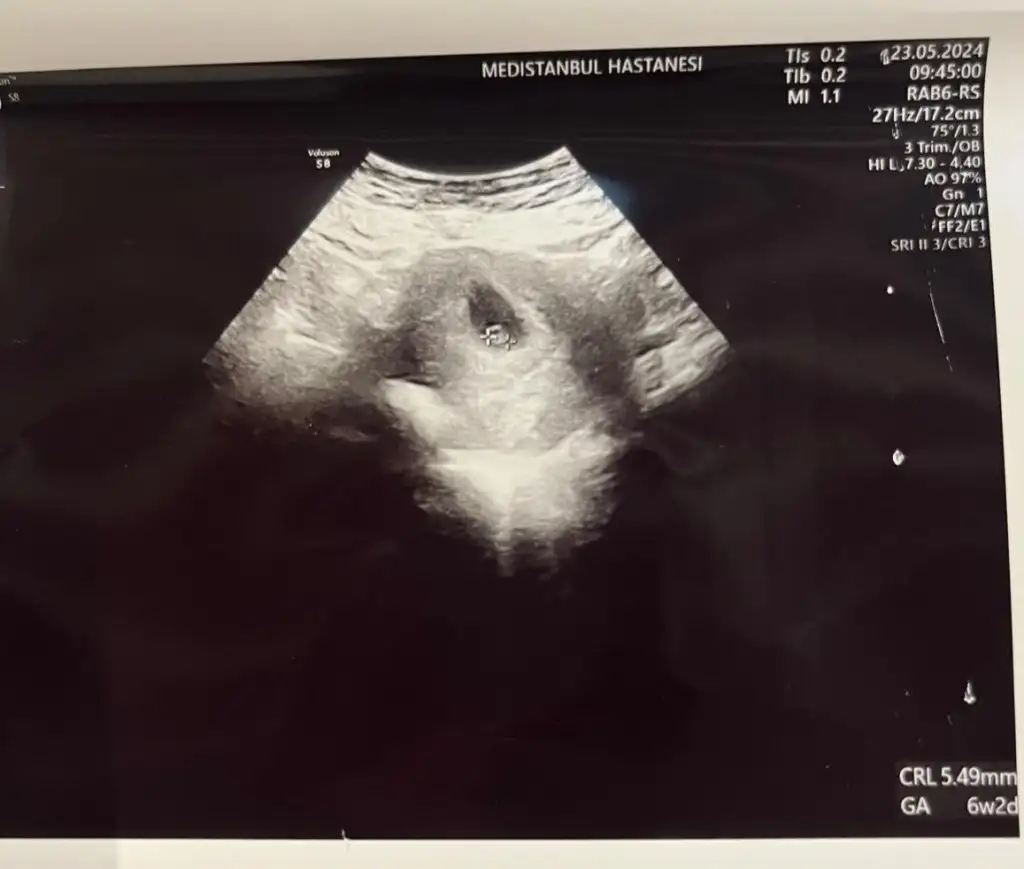

Teşekkür ederim canım CRL 3 görünüyor senin kaç mm ? Bebek için 5mm olduğunu söylediHayırlı olsun kuzum.senle aynı gün gorunuyoruz .sen de crl kaç mm

Kuzum bebek ve crl aynı şey sanırım.bana crl 4.3daha çok küçük demişti.kalp atışını baya uğraştı almak için.soninda hafif aldı .haftaya ya buraya yada ilcende bi hastaneye bidaha git dediTeşekkür ederim canım CRL 3 görünüyor senin kaç mm ? Bebek için 5mm olduğunu söyledi![]()

Galiba yanlış söyledim altta kocaman yazıyor onu görmedim de yukarda köşede yazan ufak yazılıyı gördüm 5,49mm yazıyor kuzum sanırım ona bakmam lazımdıKuzum bebek ve crl aynı şey sanırım.bana crl 4.3daha çok küçük demişti.kalp atışını baya uğraştı almak için.soninda hafif aldı .haftaya ya buraya yada ilcende bi hastaneye bidaha git dedi

Aynen canım aşağıda yazan.vajinal mi baktı karından miGaliba yanlış söyledim altta kocaman yazıyor onu görmedim de yukarda köşede yazan ufak yazılıyı gördüm 5,49mm yazıyor kuzum sanırım ona bakmam lazımdı